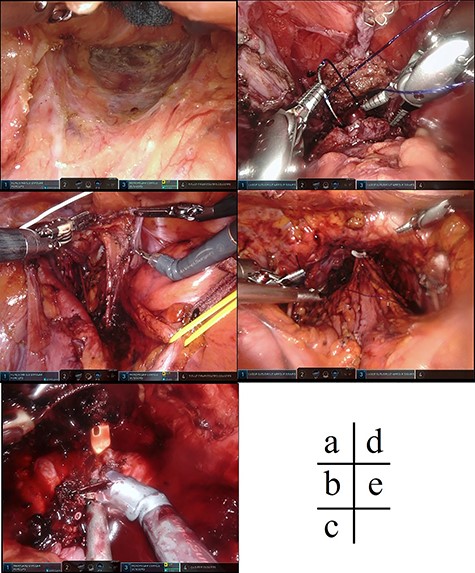

Case 1 was a 44-year-old man with a BMI of 26.9 kg/m [2], who was diagnosed as having lower rectal cancer with regional lymph node metastasis and direct prostate invasion (T4b, N1, M0 stage IIIc) (Fig. 1). The patient underwent preoperative chemotherapy followed by surgery. We docked da Vinci Xi from the lower left of the patient. The camera port was in the umbilical region, and the left 8 mm port was placed somewhat caudal from the placement of the port for rectal surgery, considering the operation procedure in urology. The surgical procedure involved dissection of the lymph node and blood vessel knot separation according to the normal procedure. Regarding rectal detachment, the posterior and lateral walls of the rectum were exfoliated as passively as possible (Fig. 2a), and the anterior wall was also exfoliated passively to the seminal vesicle position. After removal of the rectum, the oral intestinal tract was dissected with the sigmoid colon. Thereafter, dissection of the bilateral lymph nodes was performed (Fig. 2b), and the operation was transferred to urology. At that time, retargeting was set to the pelvic midline. In the urology department, resection of the prostate was performed (Fig. 2c–e), and a specimen was removed from the perineum. Subsequently, a colostomy was created and the operation was completed. The operation time was 949 min and the blood loss was 290 ml. The tumor was extending almost all around and directly invaded the prostate (Fig. 3). Pathologically, poorly differentiated adenocarcinoma including signet ring cell carcinoma was the main subject. The effect of chemotherapy was grade 0, and no effect was obtained by chemotherapy.

Intraoperative findings. (a) The rectum was detached passively, including the posterior wall of the rectum and the side wall. (b) Dissection of the lateral lymph nodes of the pelvis on both sides was performed. (c) The urethra was dissected and the urinary catheter was inserted during the prostatectomy. (d) A urethral anastomosis was performed after excision of the rectum including the prostate from the anus. (e) After specimen removal and reconstruction of the urinary tract.